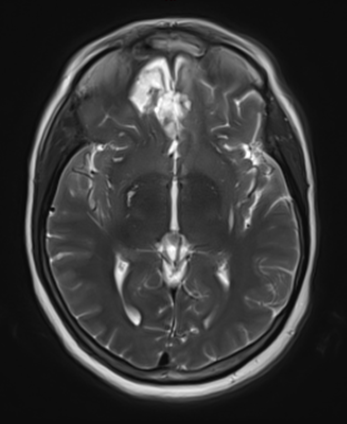

She was started on high-dose steroid and antiseizure prophylactic medicine. Surgical intervention was offered for mass effect, symptomatic relief, neurologic preservation, and histopathologic diagnosis. Dr. Gaudin performed a bifrontal craniotomy with complete resection of neoplasm through an interhemispheric and subfrontal approach. Postoperative imaging demonstrated a gross total resection without residual tumor and resolution of mass effect (Figure 1b and 2b). Intraoperative pathology was consistent with meningioma, WHO grade 1. She recovered very well, and was discharged home on postoperative day 3. On her follow-up outpatient visit, her preoperative symptoms had fully resolved, and her olfactory sense was maintained.

Figure 2b – Postoperative MRI demonstrating resolution of mass effect.